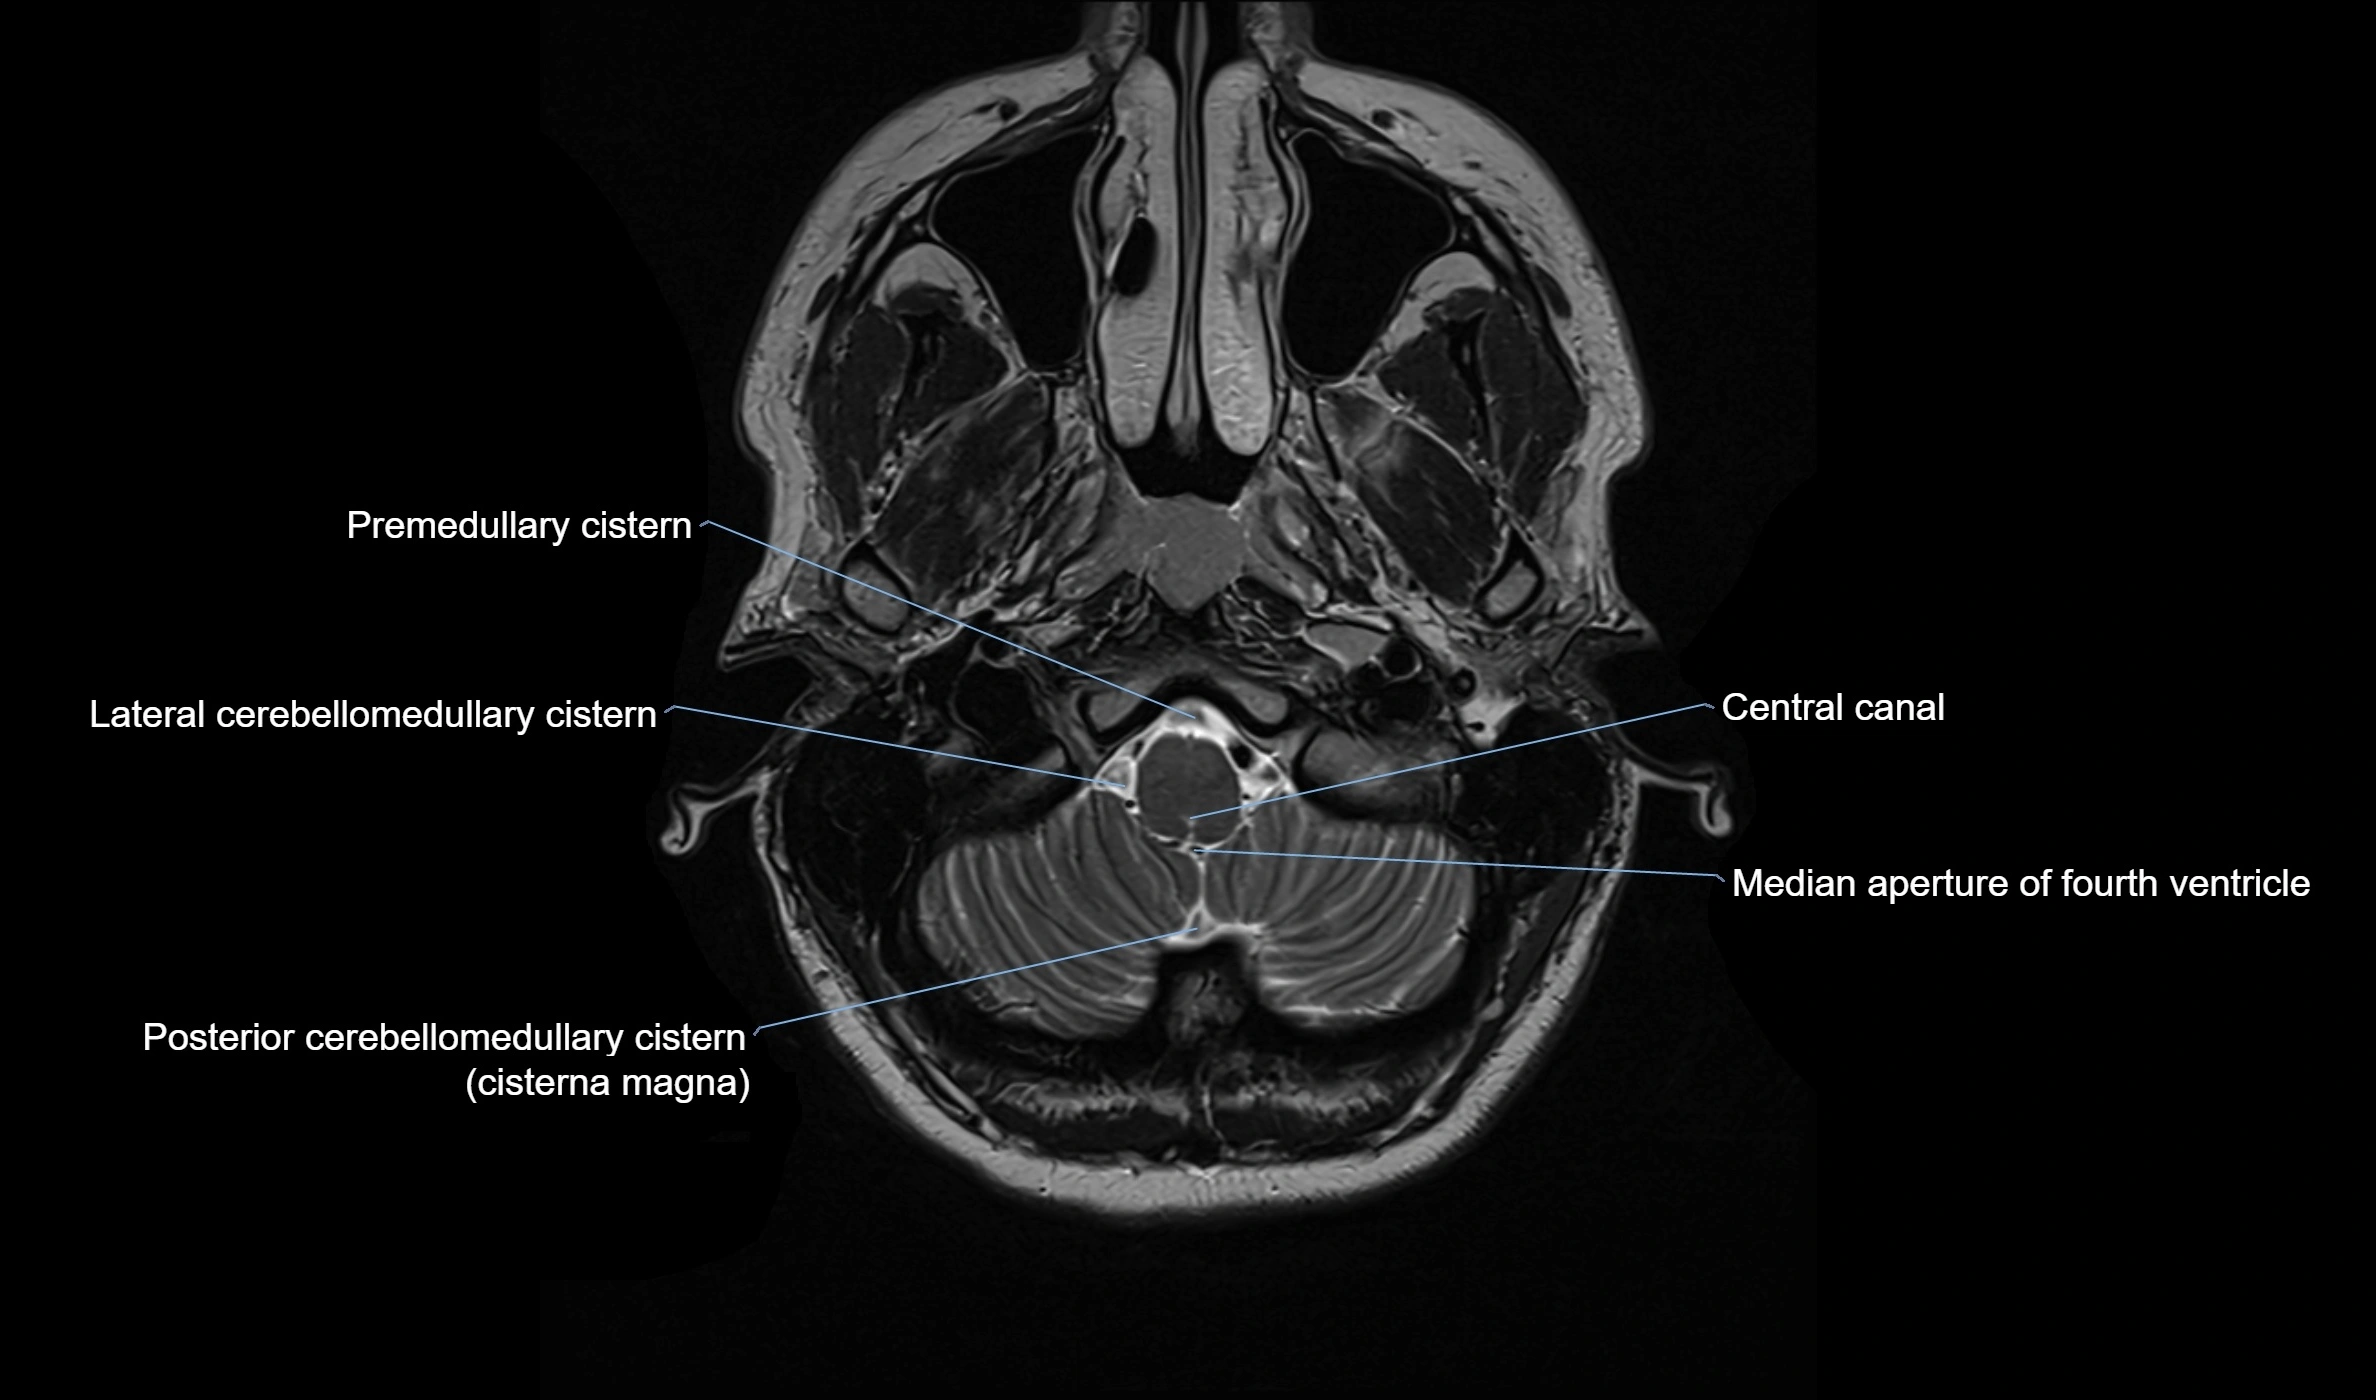

Ambient cistern

The ambient cistern is a paired, narrow, and elongated subarachnoid space located bilaterally along the lateral aspect of the midbrain. It serves as a conduit between the interpeduncular cistern anteriorly and the quadrigeminal cistern posteriorly. This cistern houses critical neurovascular structures, including parts of the posterior cerebral artery, superior cerebellar artery, trochlear nerve (cranial nerve IV), and the basal vein of Rosenthal. It plays an important role in the circulation of cerebrospinal fluid (CSF) and provides an anatomical corridor for various vessels and nerves passing around the midbrain.

MRI images

image